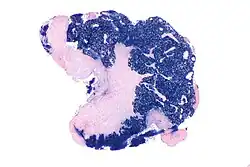

Micrograph showing a nasopharyngeal carcinoma positive for Epstein-Barr virus-encoded small RNAs (EBER).

Nasopharyngeal carcinoma, also known as nasopharyngeal cancer, is classified as a malignant neoplasm, or cancer, arising from the mucosal epithelium of the nasopharynx, most often within the lateral nasopharyngeal recess or fossa of Rosenmüller (a recess behind the entrance of the eustachian tube opening). The World Health Organization classifies nasopharyngeal carcinoma in three types, in order of frequency: Non-keratinizing squamous cell carcinoma; keratinizing squamous cell carcinoma; and basaloid squamous cell carcinoma.[15] The tumor must show evidence of squamous differentiation; with the non-keratinizing type (also known as lymphoepithelioma), the tumor is most strongly associated with Epstein–Barr virus infection of the cancerous cells.[16]